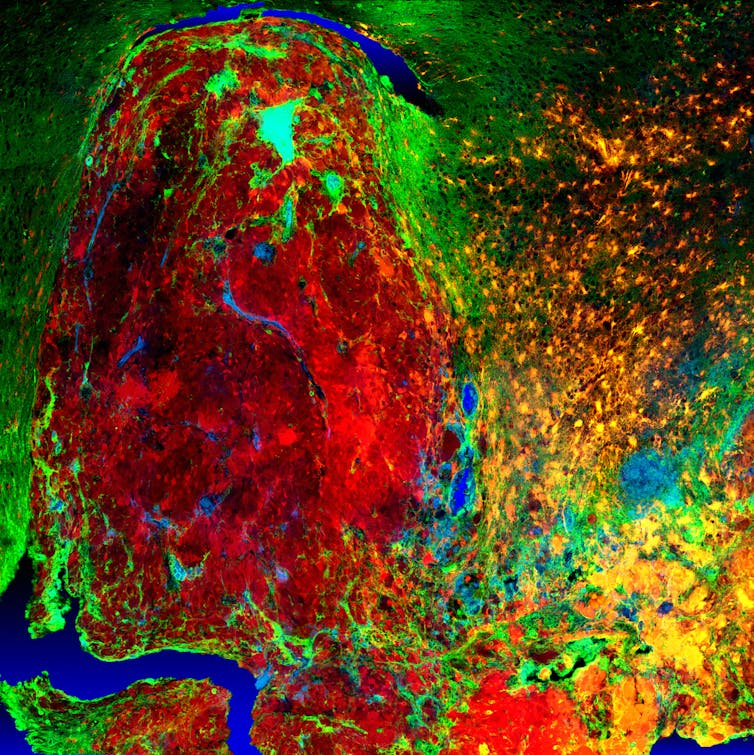

Understanding the characteristics of high-grade brain tumours is crucial to finding treatments for disease. High-resolution fluorescent imaging allows us to investigate how the normal brain cells become cancer cells and how they behave. This image demonstrates the infiltration process of the cancer cells (red) into the normal brain tissue (green).